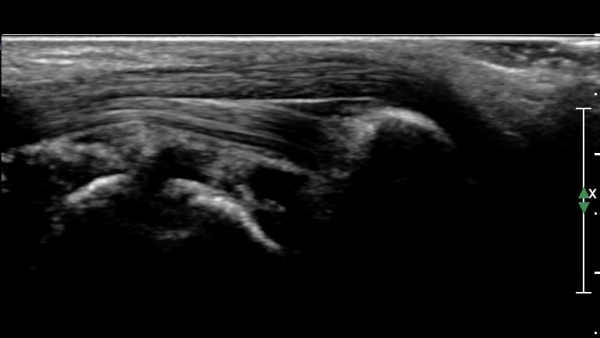

Àü°ÅºñÀδë Á¾´Ü¸é°Ë»ç»ó Àü°ÅºñÀδëÀÇ Àú¿¡ÄÚ À§Ãà°ú Á·±Ùµ¿(sinus tarsi) ¼ö¾×Àú·ù°¡

°üÂûµÈ´Ù(»çÁø 2, 3).